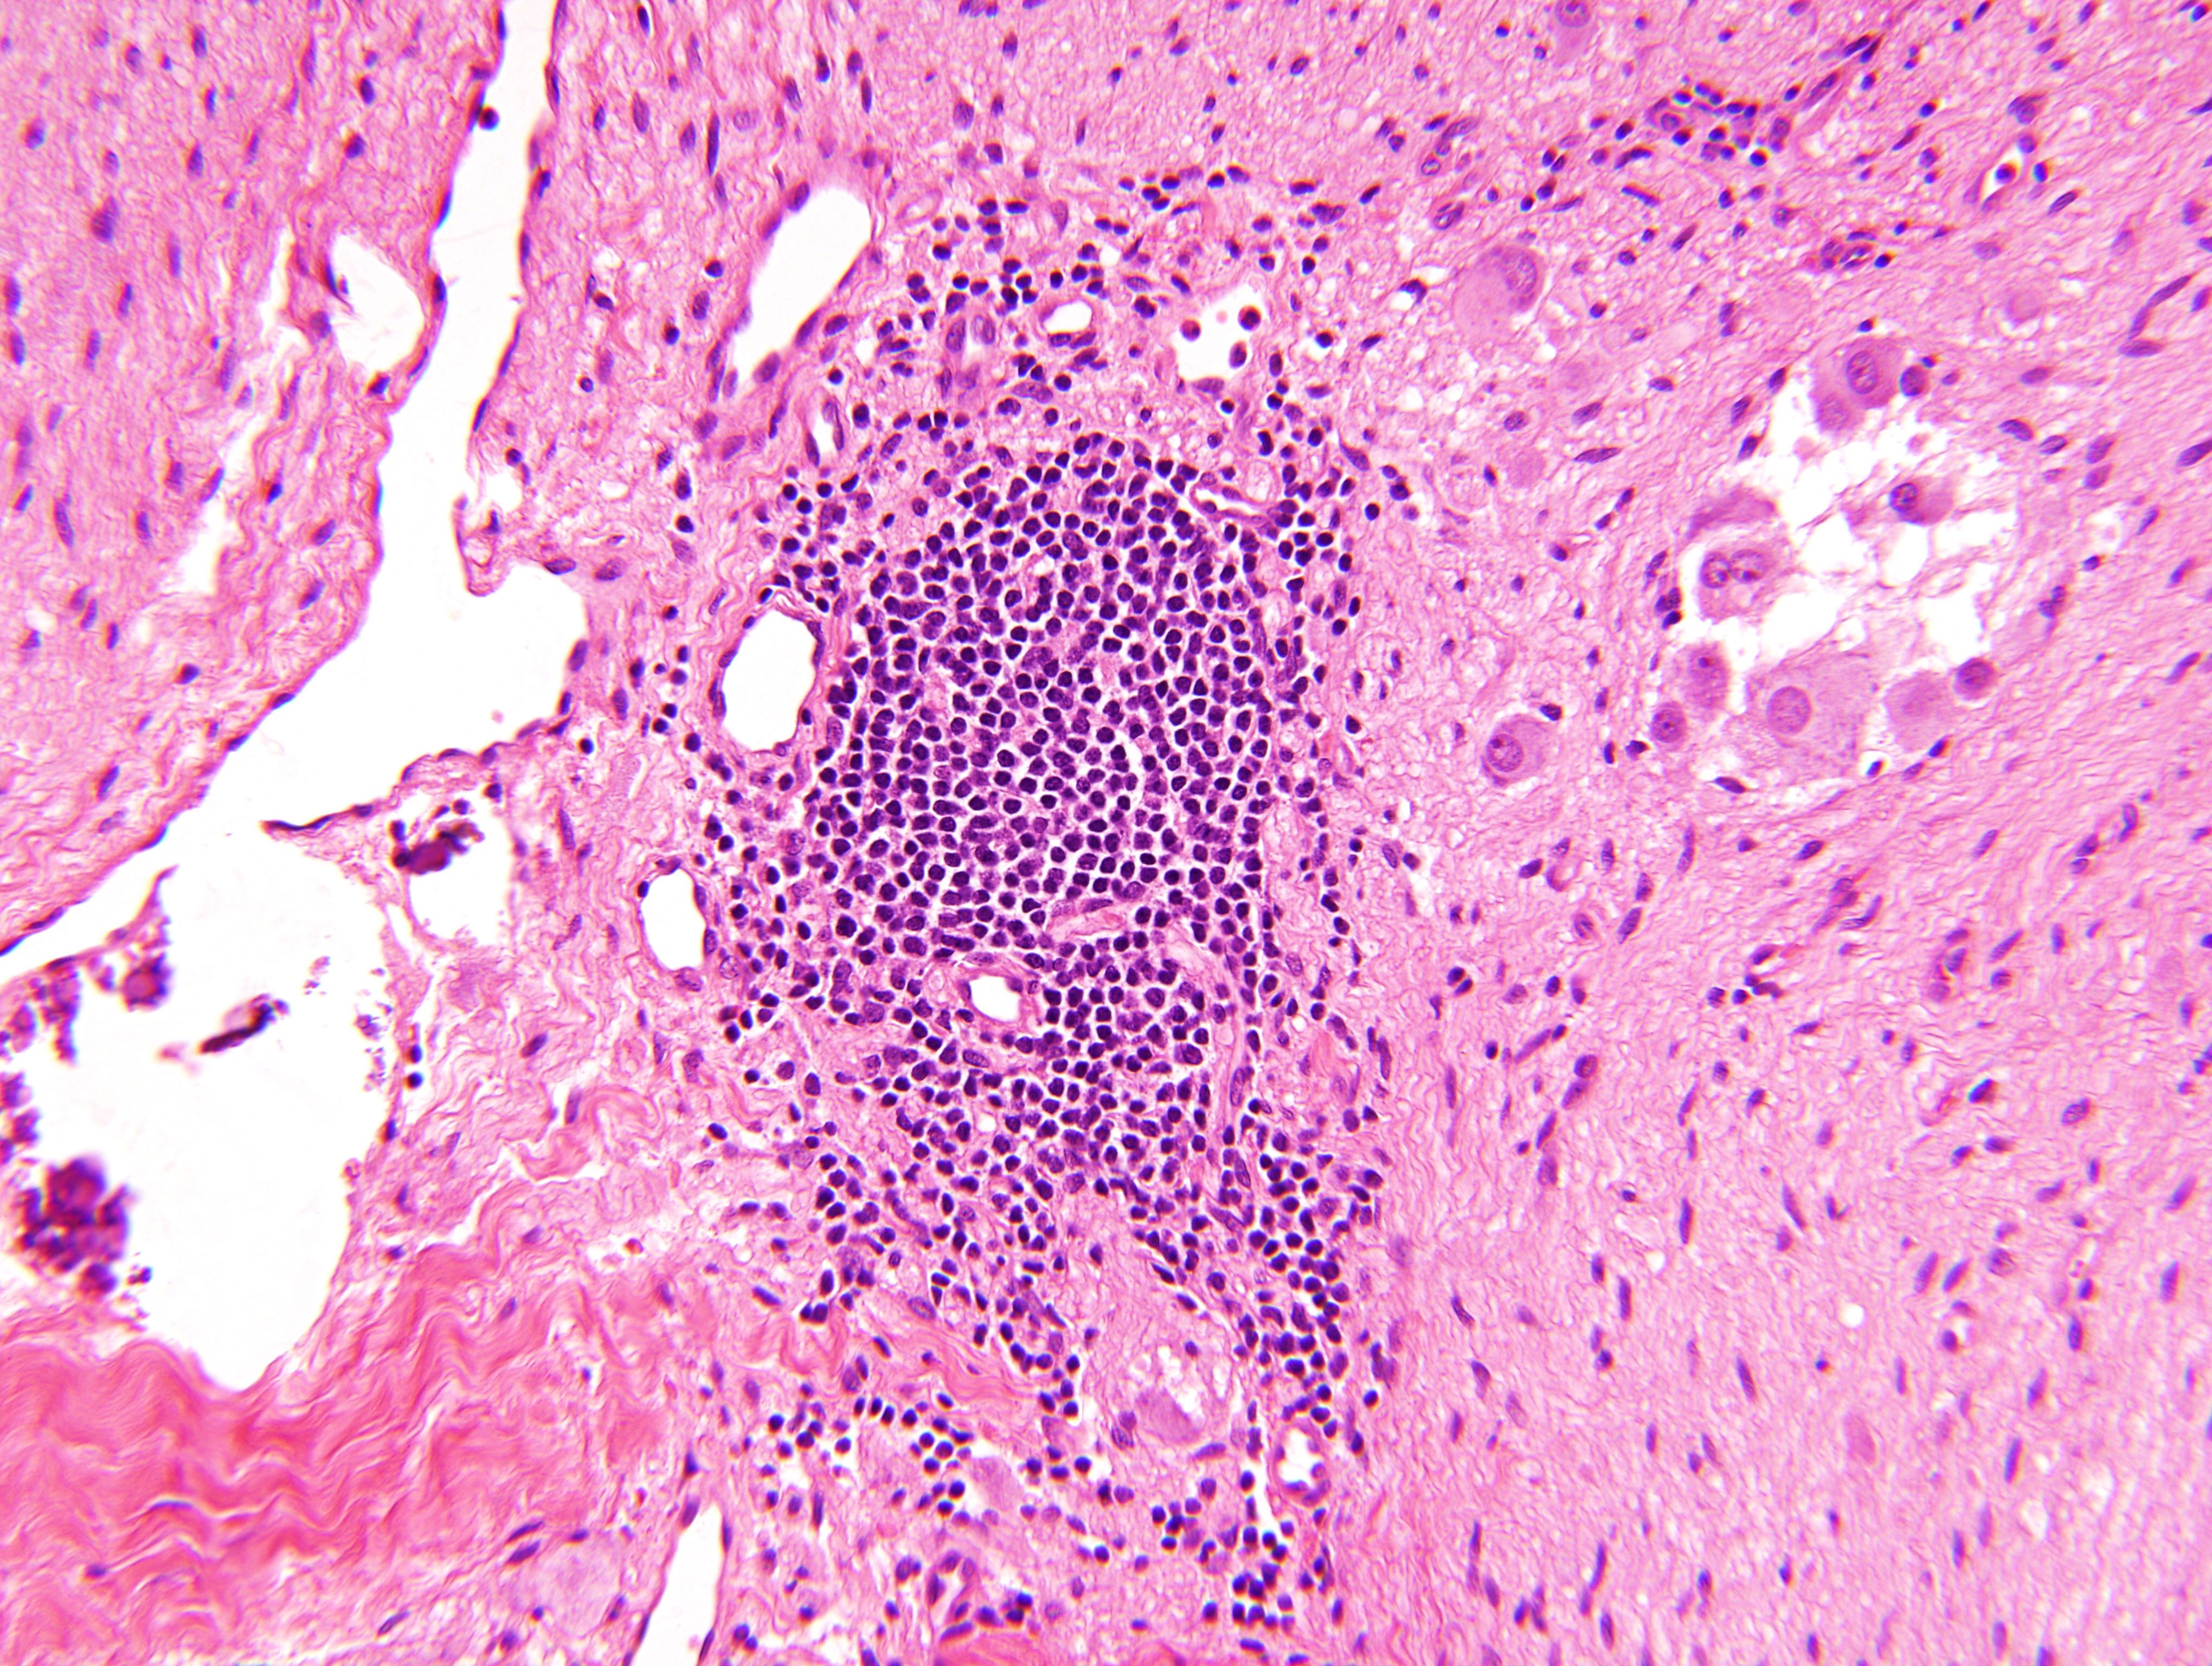

Microscopic (histologic) description

- Architecture: lobular, diffuse / solid, organoid

- Neuroblasts

- Homer Wright pseudorosettes = circular, ovoid, angular zones of pale staining neuritic cell processes surrounded by tumor cell nuclei; may rarely palisade

- Minimal cytoplasm, may have cytoplasmic tail

- Round to ovoid nuclei with stippled salt and pepper chromatin, inconspicuous nucleoli

- Ganglion cells

- Abundant granular eosinophilic cytoplasm (Nissl substance = rough endoplasmic reticulum)

- Distinct cell borders

- Nuclear enlargement, eccentric nuclei, prominent nucleoli

- May see neuromelanin pigment (brown, finely granular; rarely present), cystic degeneration, hemorrhage, dystrophic calcification

Microscopic (histologic) images

Contributed by Carmen Perrino, M.D. and Debra L. Zynger, M.D.

Intermixed type

Nodular type